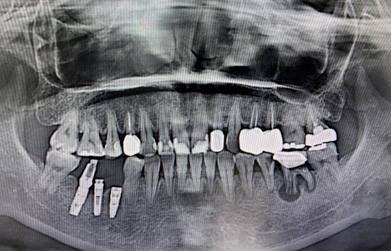

一口潔白整齊的牙齒,可以增加你的自信,讓你盡情展露笑容。但是很多人因?yàn)楦鞣N原因,從而缺失了自己的牙齒。嚴(yán)重影響的形象美觀及正常咀嚼功能。不過(guò)現(xiàn)在種植牙是非常熱門的項(xiàng)目,效果也是很不錯(cuò)的。 種植